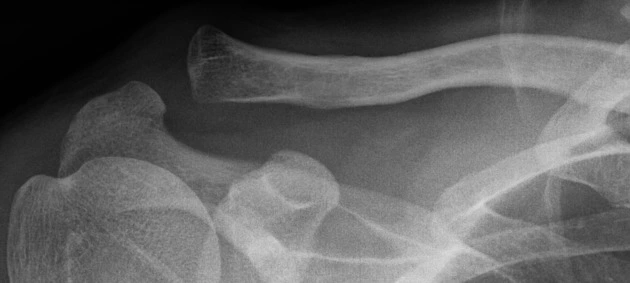

아마 내 단계는 이 중 II 단계쯤으로 짐작된다. 병원에 내원해서 엑스레이를 찍고 정확한 진단을 받아보지 않았으니 정확한 구분은 아니다. 어깨가 불편하지만 병원에 가기엔 뭔가 조금만 더 참으면 될 것 같은 정도. 아플 땐 병원 가야지 하다가 막상 시간이 나서 병원에 가려하면, '조금 더 참다가 많이 아프면 그때 가보지 뭐' 이런 정도의 상태다. 그래서 아직 병원에 가지 못했고, 불편함도 아직 가지고 있다. 일상생활은 무리 없이 하고 있다. 아마도 엑스레이 사진으로 보면 다음과 같을 것이다.

손상 단계 II. 출처 Radiopaedia.org. Case courtesy of Dr Varun Babu